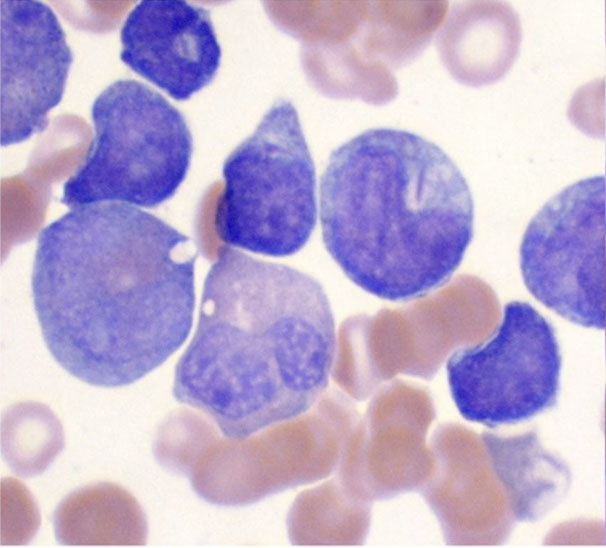

- absensce of the specific cytogenetics abnormalities seen in AML with recurrent genetic abnormalities

MC in elderly

Usually have severe pancytopenia

May appear de novo or from an evolving MDS

________________________________

IHC: w chr 5/7 del get (+) CD34, 7, TdT

________________________________

Genes: del -5 and del -7 are MC

- If NPM1 mutation identified, diagnose as AML with NPM1 mutation (despite MLD)